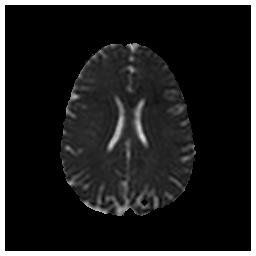

Save Image (Original Image / Clustered Image): Save only the current image to a PNG file (Figure 3). The name of the file will be the detailed title of the image.